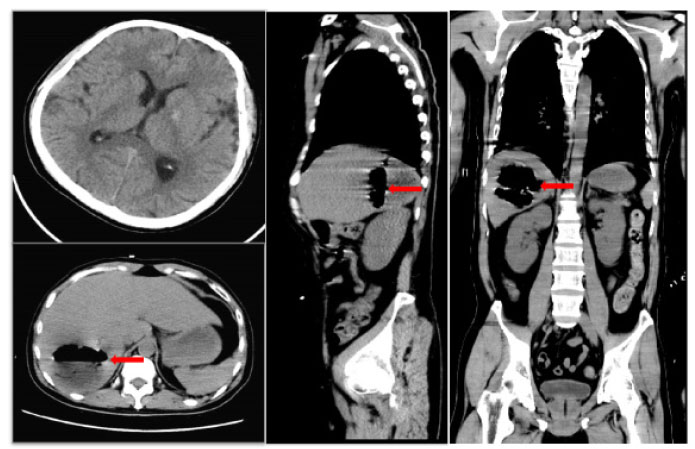

A 41-year-old male was admitted to the intensive care unit with sustained chills and fevers for 1 week and coma for 5 h. Leukocyte, neutrophil, C-reactive protein, and procalcitonin levels were high and platelet level was low. There was a significant increase in glycosylated hemoglobin, indicating undiagnosed diabetes mellitus or poor glucose control. Computed tomography (CT) revealed liver abscess with a large fluid–gas plane, but indicated no brain abnormalities (Figure 1). A diagnosis of GFPLA was made; percutaneous abscess drainage combined with anti-infective therapy was carried out, but the patient’s condition deteriorated, and bilateral pupil dilatation occurred on the next day. Immediate CT review showed brain edema and subarachnoid hemorrhage despite decrease in hepatic fluid and gas levels (Figure 2). A culture of abscess fluid and blood, along with next-generation sequencing yielded a definitive diagnosis of K. pneumoniae infection (Figures 3). Anaerobic and fungal cultures were negative. Anti-infective therapy based on drug-sensitive experiments was administered (imipenem cilastatin 2 g, every 6 hours), but the treatment was not effective and the patient eventually died of progressive cerebral swelling, herniation, and pneuomocrania (Figure 4).

Initial brain CT scan shows no abnormalities, while sagittal and axial abdominal CT scans reveal a hepatic abscess with high gas and fluid levels in the right lobe. Red arrow: a large amount of gas is seen in the cavity of the liver abscess. CT: computed tomography.